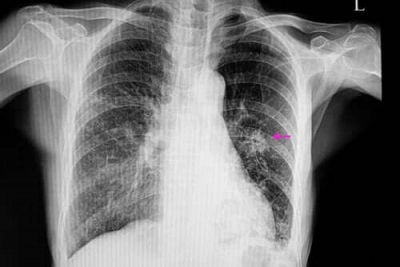

O nódulo pulmonar é definido como uma imagem arredondada ou oval, bem delimitada, localizada dentro do pulmão, com até 3 centímetros de diâmetro. Quando a lesão tem mais de 3 cm, passa a ser chamada de “massa pulmonar”, o que requer uma avaliação ainda mais cuidadosa.

Esses nódulos são geralmente encontrados em exames de imagem do tórax, como na tomografia computadorizada (TC).

Ao encontrar um nódulo em um exame, o médico segue um processo sistemático para avaliar o risco de malignidade. Essa avaliação considera o tamanho do nódulo, o formato e as bordas.

Por exemplo, nódulos menores que 6 mm têm baixo risco de serem câncer. Bordas lisas e regulares geralmente sugerem benignidade, enquanto bordas irregulares ou espiculadas podem levantar suspeita de malignidade.

O especialista também deve ficar atento à composição do nódulo. Nódulos sólidos ou calcificados são mais frequentemente benignos e nódulos de vidro fosco (mais esbranquiçados e menos densos) podem necessitar de acompanhamento mais próximo.